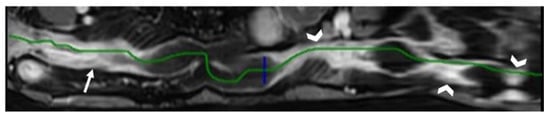

- Minordi, L.M.; Larosa, L.; Brizi, M.G.; Armuzi, A.; Manfredi, R. Length of the healthy and pathological small intestine in patients with Crohn’s disease: Calculations using computed tomography and magnetic resonance enterography. Diagn. Interv. Radiol. 2023, 29, 24–28. [Google Scholar] [CrossRef]